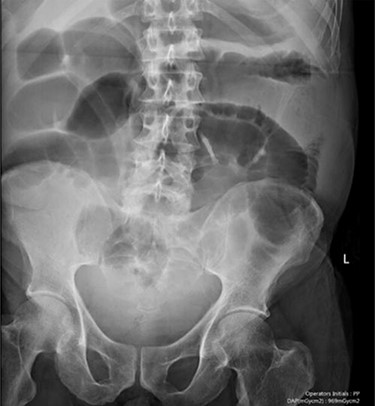

Blood tests on admission were unremarkable, with normal electrolytes levels and lactate. A plain abdominal film showed a typical appearance of caecal volvulus, with an inverted ‘comma sign’ (Fig. 4). A CT scan of the abdomen and pelvis with intravenous contrast was reported as sigmoid volvulus with the involved loops sitting predominantly in the right upper quadrant immediately inferior to the liver (Fig. 5).

Case two: a plain abdominal film showing dilated large bowel and the ‘inverted comma’ sign associated with caecal volvulus.